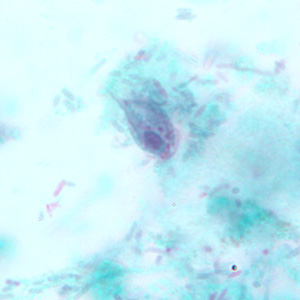

E.histolytica cyst

four nuclei and a chromatoid body with blunt ends